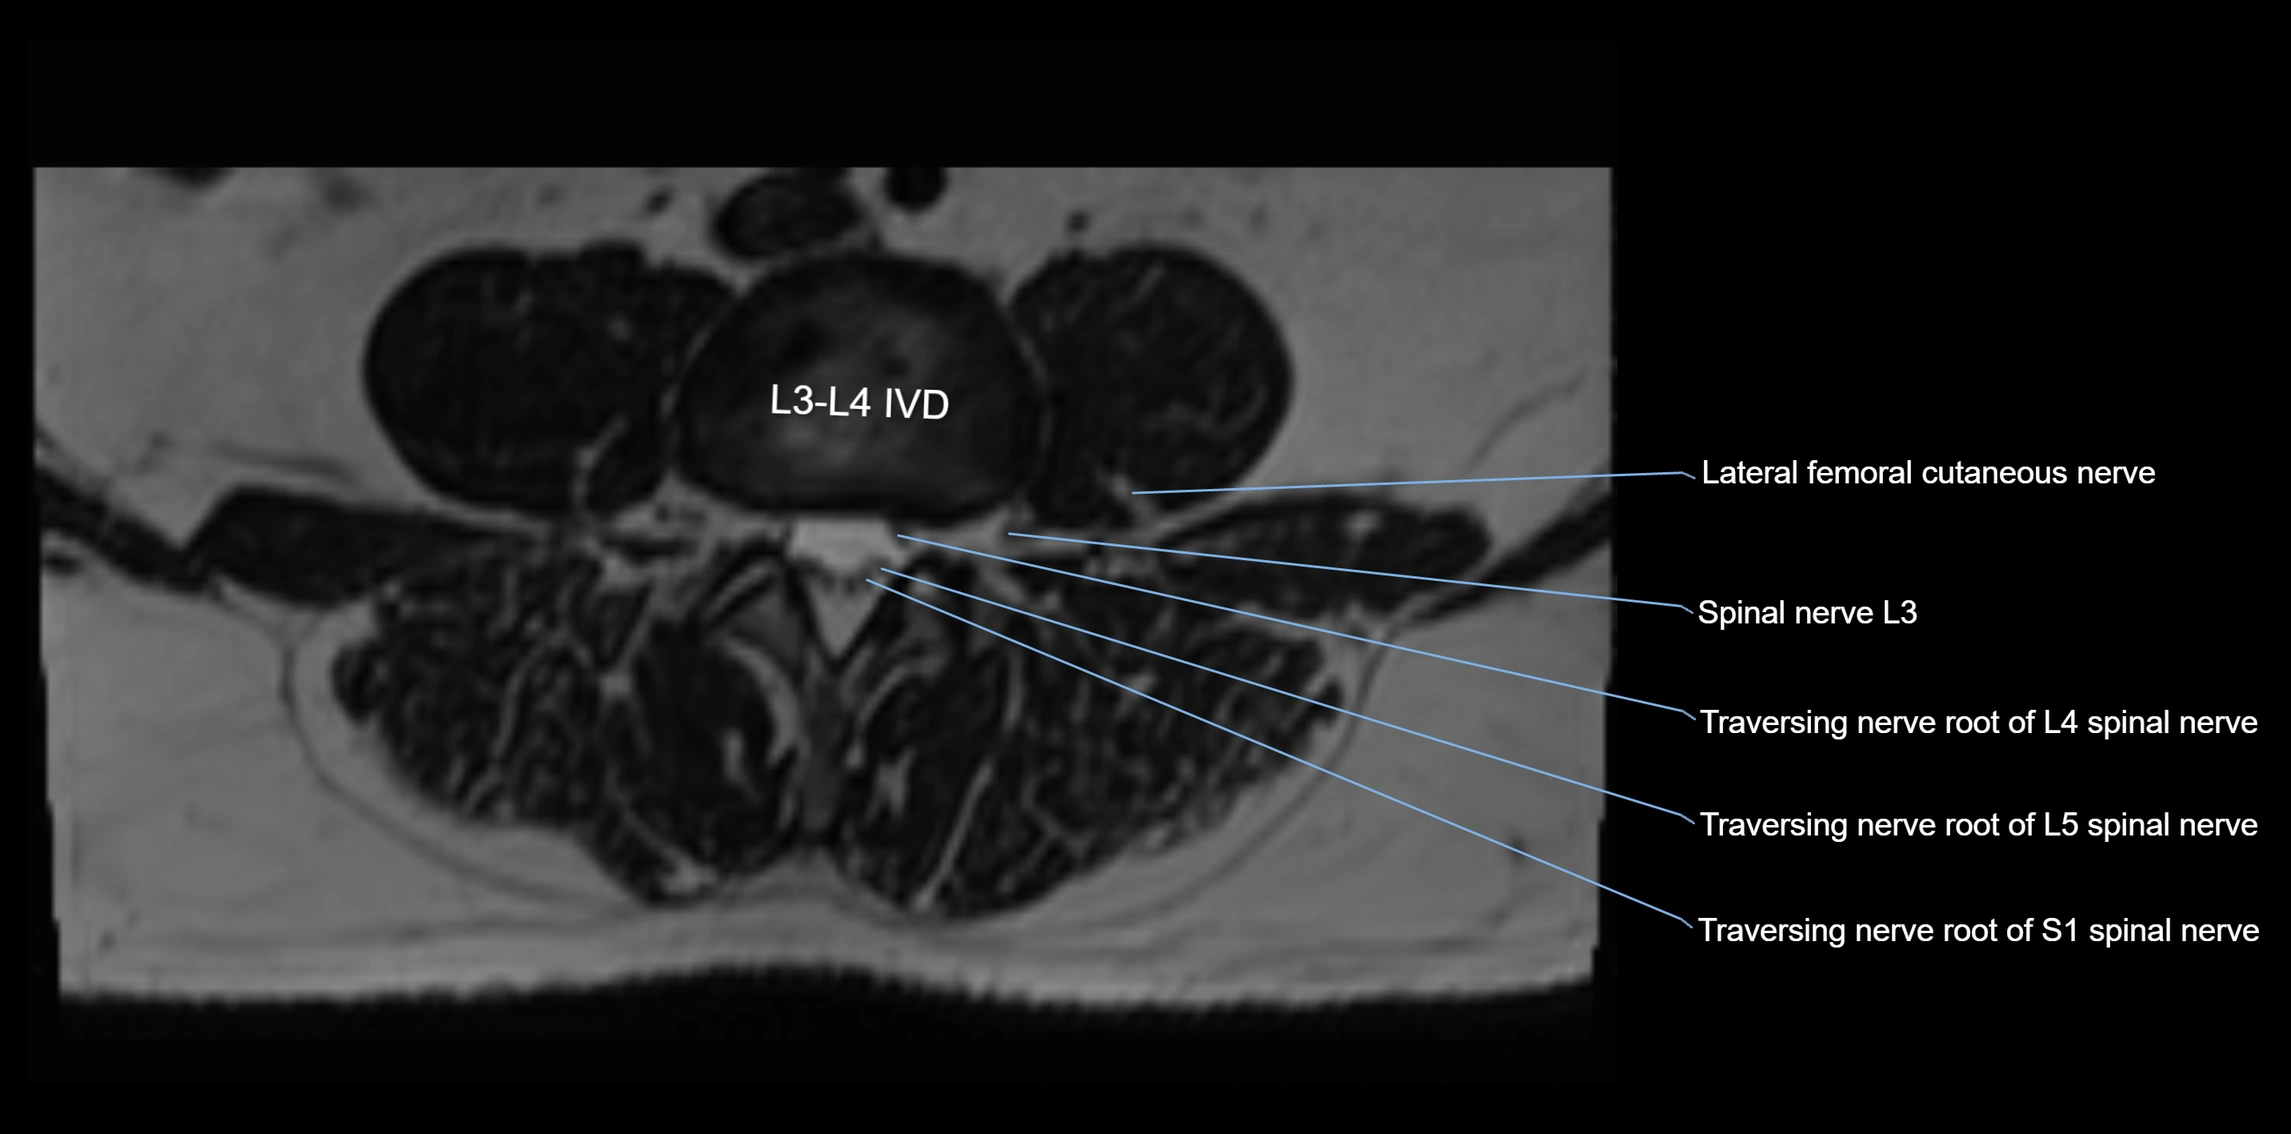

MRI Appearance

T1-weighted images:

• Nerve appears as a very thin low-to-intermediate signal intensity structure

• Surrounded by bright fat, aiding visualization

T2-weighted images:

• Nerve shows intermediate to mildly hyperintense signal compared to muscle

• Pathological involvement appears brighter

STIR (Short Tau Inversion Recovery):

• Normal nerve appears dark

• Inflamed or entrapped nerve appears bright hyperintense

3D T2 SPACE / CISS:

• Nerve appears intermediate to mildly hyperintense compared to muscle

• Surrounded by bright fat or CSF, improving visualization

• Best sequence for mapping small pelvic nerves such as the anococcygeal